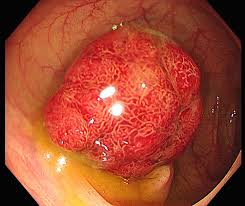

① 대장내시경 검사

가장 정확한 진단 방법은 대장내시경 검사입니다. 용종이 발견되면 절제 후 조직검사를 통해 암 여부를 확인할 수 있습니다.